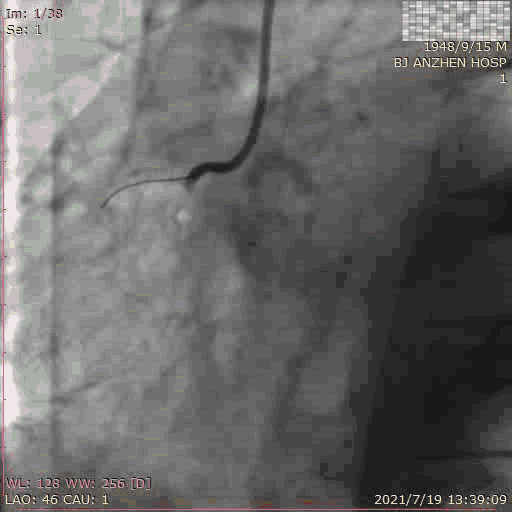

PCI过程:术中使用 7F AL 0.75 Guiding,顺利于RCA植入2.5*18mm支架,术后予双联抗血小板治疗,恢复良好。